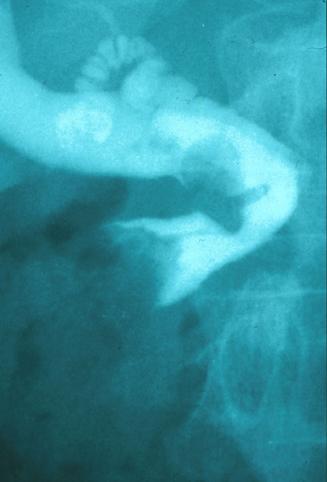

질환(병리주체)의 분류 악성 상피성종양/선암

부위(장기별) 십이지장/유두부

검사방법 X-P

종양의 최대경(밀리미터) 20~24